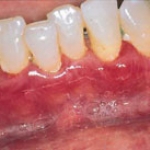

phuong-phap-moi-dieu-tri-nuouTụt lợi là quá trình lộ bề mặt chân răng do sự di chuyển về phía chóp chân răng của lợi. Tụt lợi là điềm báo trước sự mất cement chân răng, lộ ngà, tăng cảm giác và giảm thẩm mỹ. Phương pháp điều trị tụt lợi tốt nhất là ghép nha chu chân răng.

Phẫu thuật mới điều trị tụt lợi

• Bệnh nhân có thể được ghép tổ chức bù lại phần lợi bị tụt để che phủ chân răng và cổ răng, tránh mòn tổ chức cứng của răng, tổ chức ghép có thể lấy ở vùng hàm ếch hoặc vùng răng lân cận. Phẫu thuật ghép tổ chức nha chu là phương pháp tốt nhất để phục hồi thẩm mỹ và chức năng cho người bệnh. Các phương pháp thường được sử dụng để che phủ chân răng: